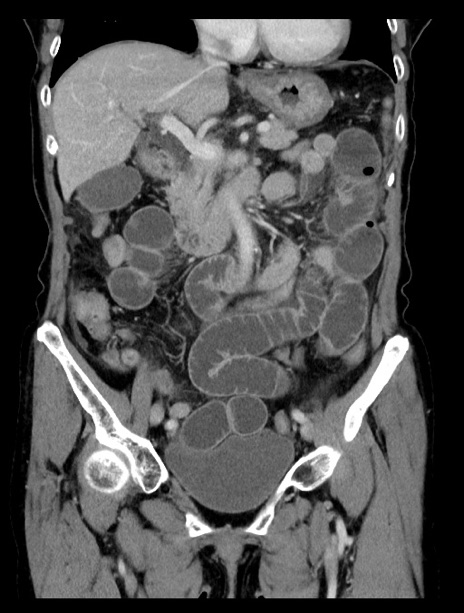

症例23(冠状断像)

【症例】70歳代女性

【主訴】下腹部痛・嘔吐

【現病歴】2日前より腹痛あり。昨日嘔吐あり。症状改善しないため来院。

【既往歴】胃GISTに対して胃部分切除後。

【身体所見】BT 37.1℃、BP 128/77mmHg、腹部:平坦・軟、下腹部に圧痛あり。

【データ】WBC 10200、CRP 0.31